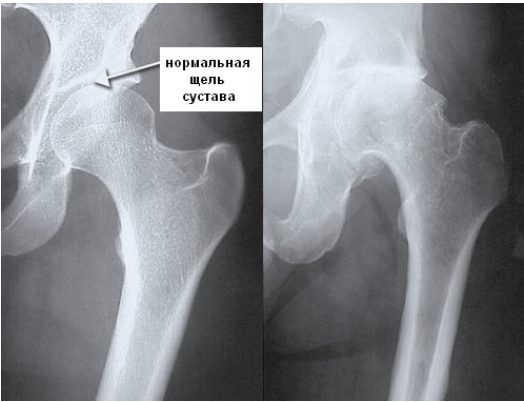

Остеоартроз

Неприятные ощущения в суставах иногда свидетельствуют о развитии остеоартроза. Для патологии характерно постепенное разрушение хрящевых тканей, выполняющих функции амортизатора, предупреждающих повреждение костей во время движения. Заболевание возникает из-за избыточного веса, гормональных нарушений, частого переохлаждения, тяжелых физических нагрузок. Чтобы стабилизировать суставы во время передвижения, в них начинают разрастаться костные пластинки. Острыми краями они сдавливают кровеносные сосуды, чувствительные нервные окончания, вызывая сильные боли.

Остеоартрозом поражаются как крупные (голеностоп, локти, плечи, колени), так и мелкие сочленения (лучезапястные, плюснефаланговые). Помимо кручения в суставах, возникают и такие симптомы: